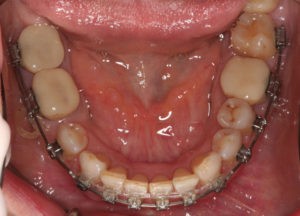

Для предварительной подготовки были привлечены пародонтолог и ортопед, поскольку отсутствие нескольких зубов, заболевание пародонта и дефекты твердых тканей зубов сопутствовали основной патологии. Проведены пародонтологические процедуры, вылечен кариес и его осложнения, изготовлены временные коронки для зубов с большим разрушением. На фото — временные коронки на боковых зубах.